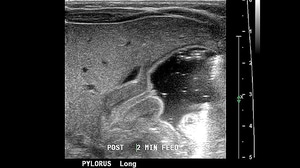

11 Infant Abdominal EmergenciesThis slideshow will bolster your differential while providing salient insights for some of the more common infantile intestinal emergencies.